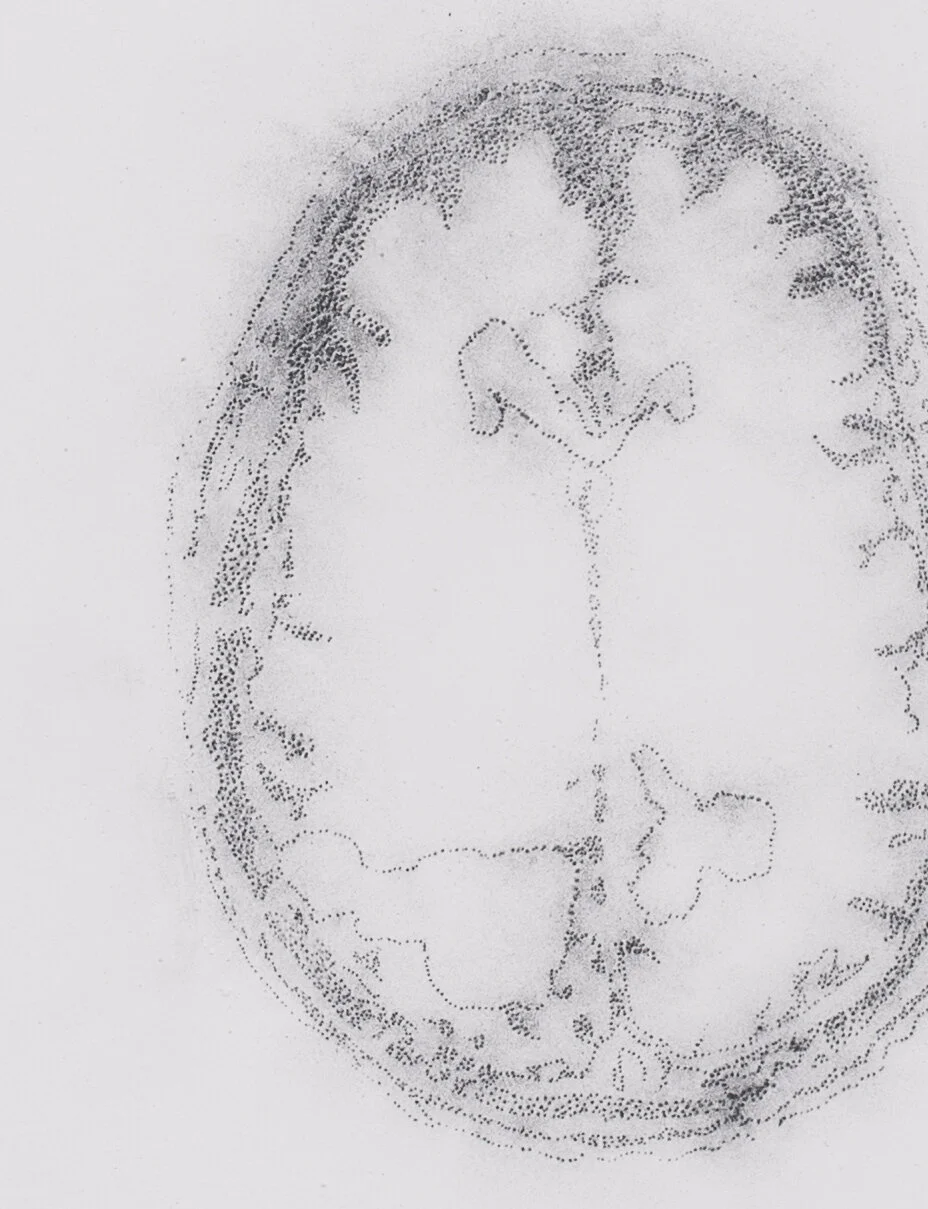

Eloquent Brain

The doctors pointed to areas on my dad’s MRI’s and called them eloquent. Eloquent, like the silence falling after a great orator has spoken a final word.

“Eloquent cortex is a term that refers to specific brain areas that directly controls function, thus damage to this area generally produces major focal neurological defects”.

Eloquent were the parts of my dad’s brain that executed voluntary motor movements, the parts concerned with walking, standing up from a chair, and kissing cheeks. They are the areas that are concerned with the production and reception of speech. To know words and speak them with our mouths. To understand the jumble of sounds coming to us on air waves as sentences. The areas that know how to make sense of signals coming from the retina, giving the ability to see. It is the eloquent cortex that also controls autonomic responses like breathing.

These drawings are maps. They are a way of peering into unseen territories and marking them in an effort to understand an abstraction. A mapping of an x-ray of my twelve-year-old torso undergoing treatment for scoliosis, a severe curvature of the spine, or the imaging of my father’s brain tumor as it grew to overcome him. The drawings open up the body to be viewed through its interior, to be seen in its particular vulnerability. They mark the edge of a body, attempting to touch the physical boundaries of a being, in what feels like the pursuit of a ghost.